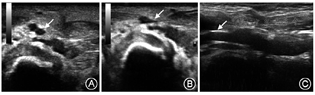

16例患儿因坏死性小肠结肠炎合并多器官衰竭死亡2例,死亡时间分别为置管后35 d和66 d;4例电话随访,10例门诊随访,中位随访时间622(22~1 082) d ,门诊随访病例均行穿刺部位彩超检查。所有随访患儿两侧下肢对称,无水肿、感觉或运动障碍等异常;彩超复查2例右股静脉穿刺患儿出现穿刺处血管轻度狭窄(图1);1例右股静脉出现中度狭窄,表现为局部管壁增厚,管径减小(图2)。其中,深静脉中度狭窄患儿置管术耗时95 min,导管留置时间为19 d;余患儿相应部位深静脉血流均通畅,无静脉血栓形成。

新生儿静脉细,直接穿刺是否会造成远期狭窄或闭塞是目前关注的问题。穿刺血管狭窄及栓塞的发生率随穿刺次数增多、导管留置时间过长而增高[20,21]。本组病例出院时(包括2例死亡患儿)穿刺部位与穿刺侧肢体体格检查均无异常,随访时彩超复查穿刺处深静脉有3例(3/10)出现轻-中度狭窄,表现为局部管壁增厚、管径减小,但血流通畅,远期预后还有待随访。